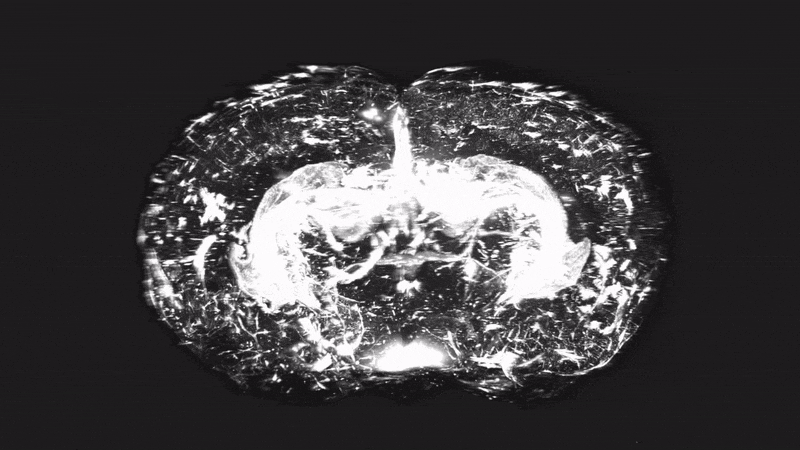

Microscopy images of brain vasculature showing blood-brain barrier structure and protein transport

We recently developed cell type-specific and plasma proteome labeling techniques to reveal an unexpected degree and diversity of protein transport across the healthy blood-brain barrier (BBB), reaching neurons, microglia, and other brain cell types.

We are now deciphering the identities, functions, and mechanisms of protein and immune cell signaling across the BBB in health and disease. We seek to understand what distinguishes a protein or immune cell that can enter the brain from those that cannot.